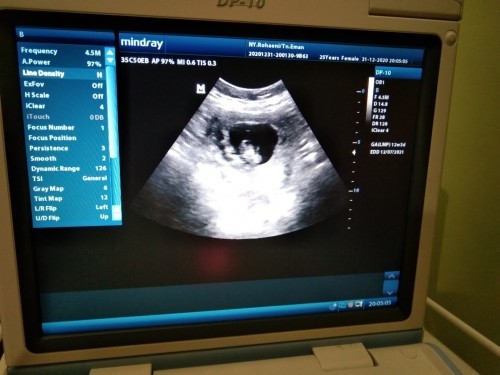

Mau tanya dong bunda aku hamil ga mau mkn lemas bawaan nya muntah trus gimna yg cra nya ilangin mual